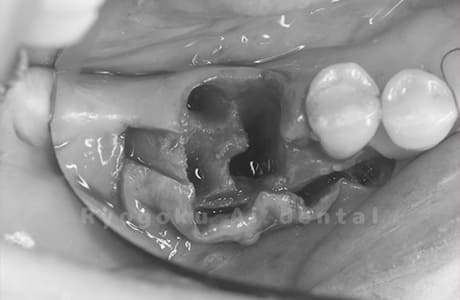

Case12

- 原因

- 左下7番歯牙破折

-

- 治療内容

- インプラント治療

- 治療費用

- 約600,000円

左下の奥歯が痛いとのことでご来院された患者様です。歯が完全に割れており、保存が不可能であったため、抜歯を行い、その際に骨に変わるお薬を入れ、十分な治癒を待ってからインプラント治療を行いました。経過良好で、大変満足されました。

<リスク・副作用>

治療後、痛みや違和感、出血、腫れなどが出る事があります。喫煙者、糖尿病などの方の場合、歯が生着しない場合があります。